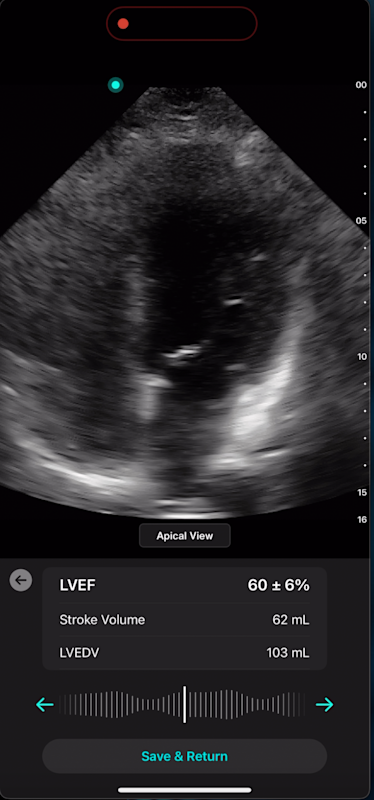

Cardiac AI

With Exo’s Cardiac AI, you can measure left ventricular ejection fraction (LVEF) and stroke volume in a few heartbeats in both parasternal long axis (PLAX) and apical four-chamber (A4C) views, making it easier than ever for POCUS users to get to answers.